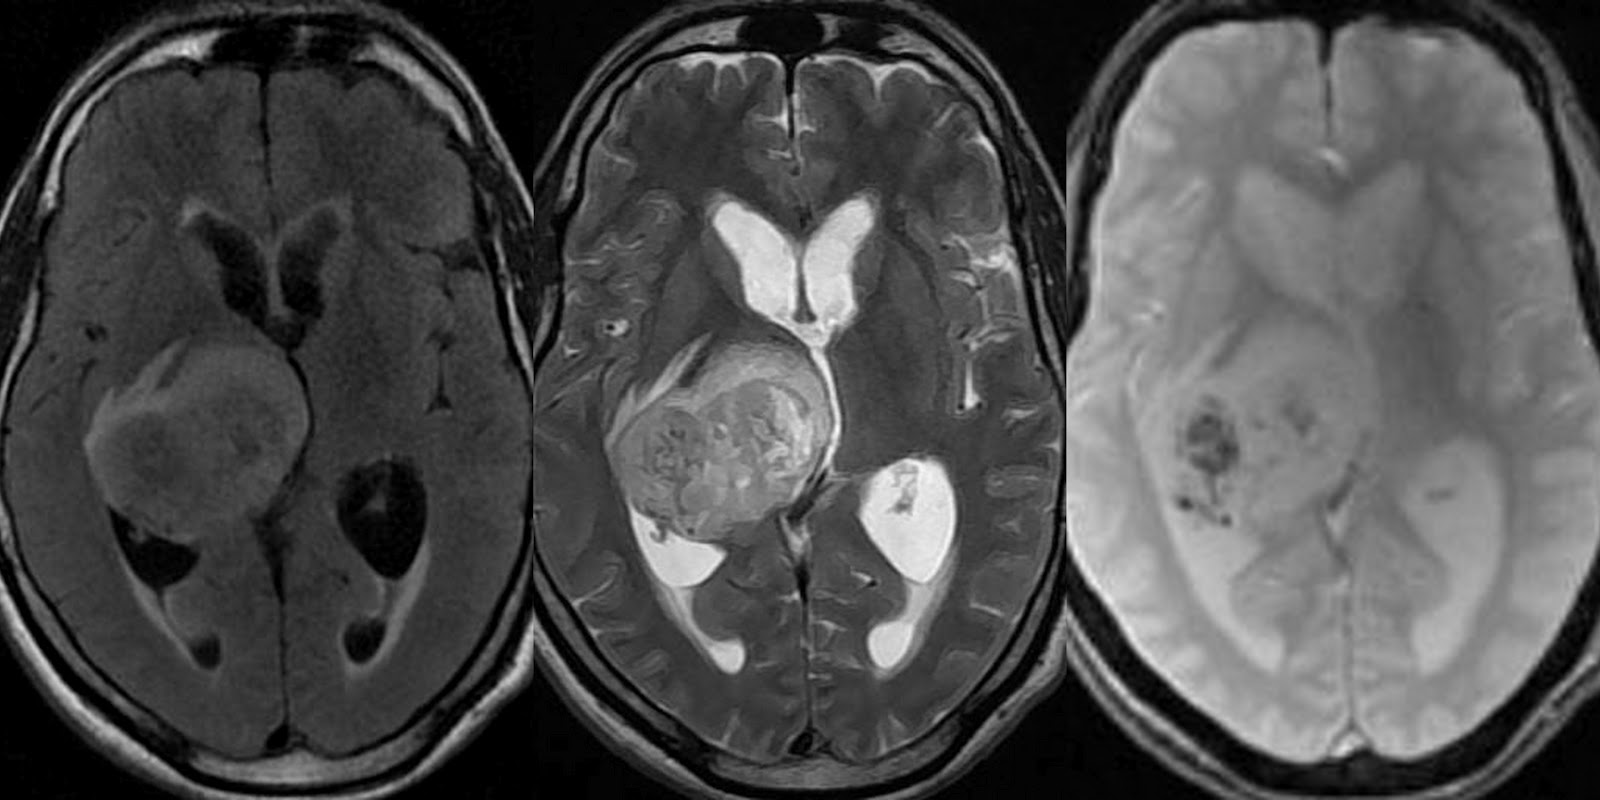

Cáncer Cáncer de cerebro

Conexión entre el tratamiento de Glioma (Cáncer en el cerebro) y el glutatión

Los gliomas son quizas el tipo de cancer de cerebro mas interesante. Estan clasificados en distintas formas incluyendo el tipo, grado y localizacion. Son tambien